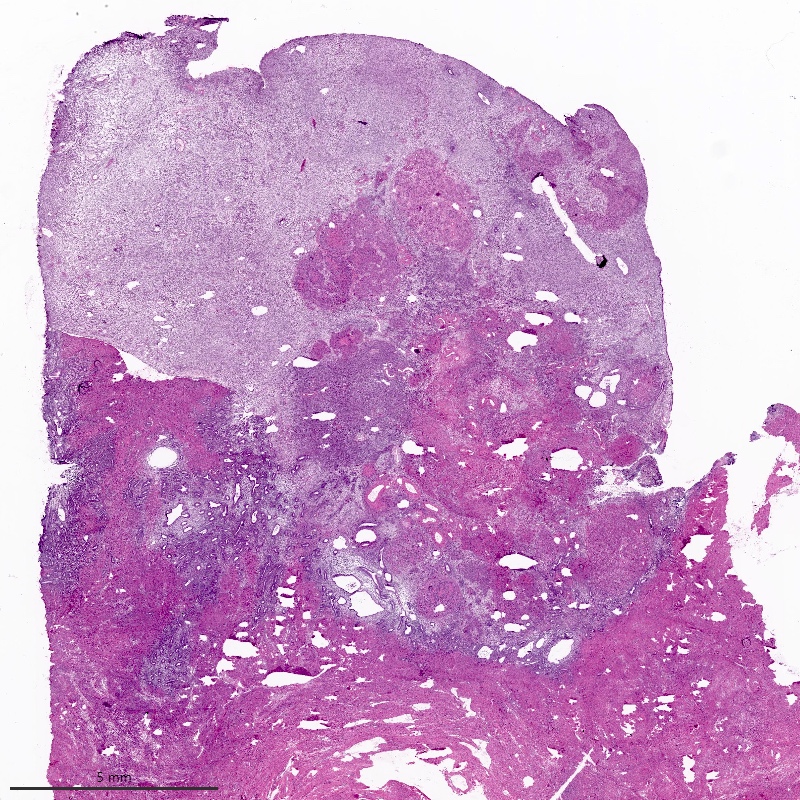

Microscopic (histologic) description

- Irregular cellular islands, forming permeative tongue-like pattern of myometrial invasion with frequent vascular invasion

- Monotonous oval to spindle cells with minimal cytologic atypia, vesicular chromatin and scant cytoplasm

- Mitotic count is usually low (< 5/10 high power fields), necrosis is usually absent

- Tumor cells may whorl around delicate arteriolar type vessels, reminiscent of proliferative phase endometrial stroma

- May have admixed collagen bands / plaques and foamy histiocytes

- May have smooth muscle differentiation, particularly in a starburst morphology, with collagen bands radiating towards the periphery of the nodule

- Other reported types of differentiation: fibromyxoid / fibrous, sex cord-like, epithelioid, rhabdoid, endometrioid glands, pseudopapillae, clear cells, bizarre cells, adipose tissue (Mod Pathol 2016;29:S92)

Microscopic (histologic) images

Contributed by Elizabeth Kertowidjojo, M.D., Ph.D., M.P.H. and Ayse Ayhan, M.D., Ph.D.

D. Low grade endometrial stromal sarcoma. The tumor shows a polypoid component, as well as a characteristic permeative tongue-like invasion pattern seen on low power. The presence of invasion rules out an endometrial stromal nodule (answer B) and cellular leiomyoma (answer A). The lack of any glandular component rules out endometrioid carcinoma (answer C). While low grade endometrial stromal sarcoma can have sex cord-like differentiation, the presence of conventional low grade endometrial stromal sarcoma rules out uterine tumor resembling ovarian sex cord tumor (answer E).